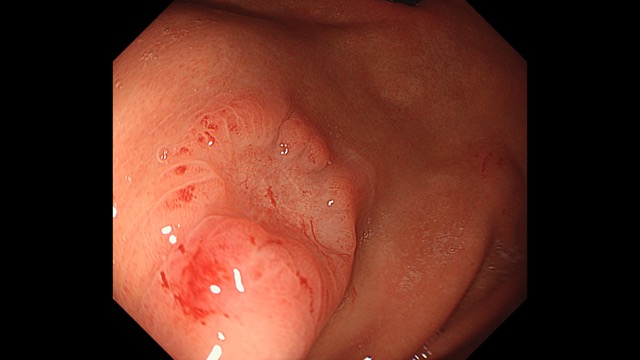

胃001